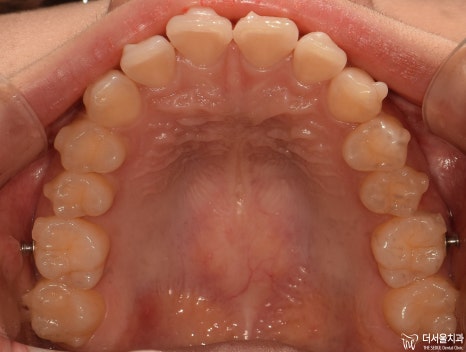

먼저 교합면에서 보게 되면, 앞니들의 총생이 관찰됩니다.

그래서 인비절라인 클린첵 시뮬레이션으로 확인을 해야 됩니다.

인비절라인 클린첵 시뮬레이션 진행

치열이 변화가 되는것을 한 눈에 볼 수 있죠? 이게 인비절라인의 장점입니다.

다행히 비발치교정 으로 진행이 가능하다는 판단이 나왔으며 어금니들의 위치 이동에 따라서

일부 공간을 확보하면서 앞니들을 뒤로 넣는 치료 계획이 수립되었습니다.